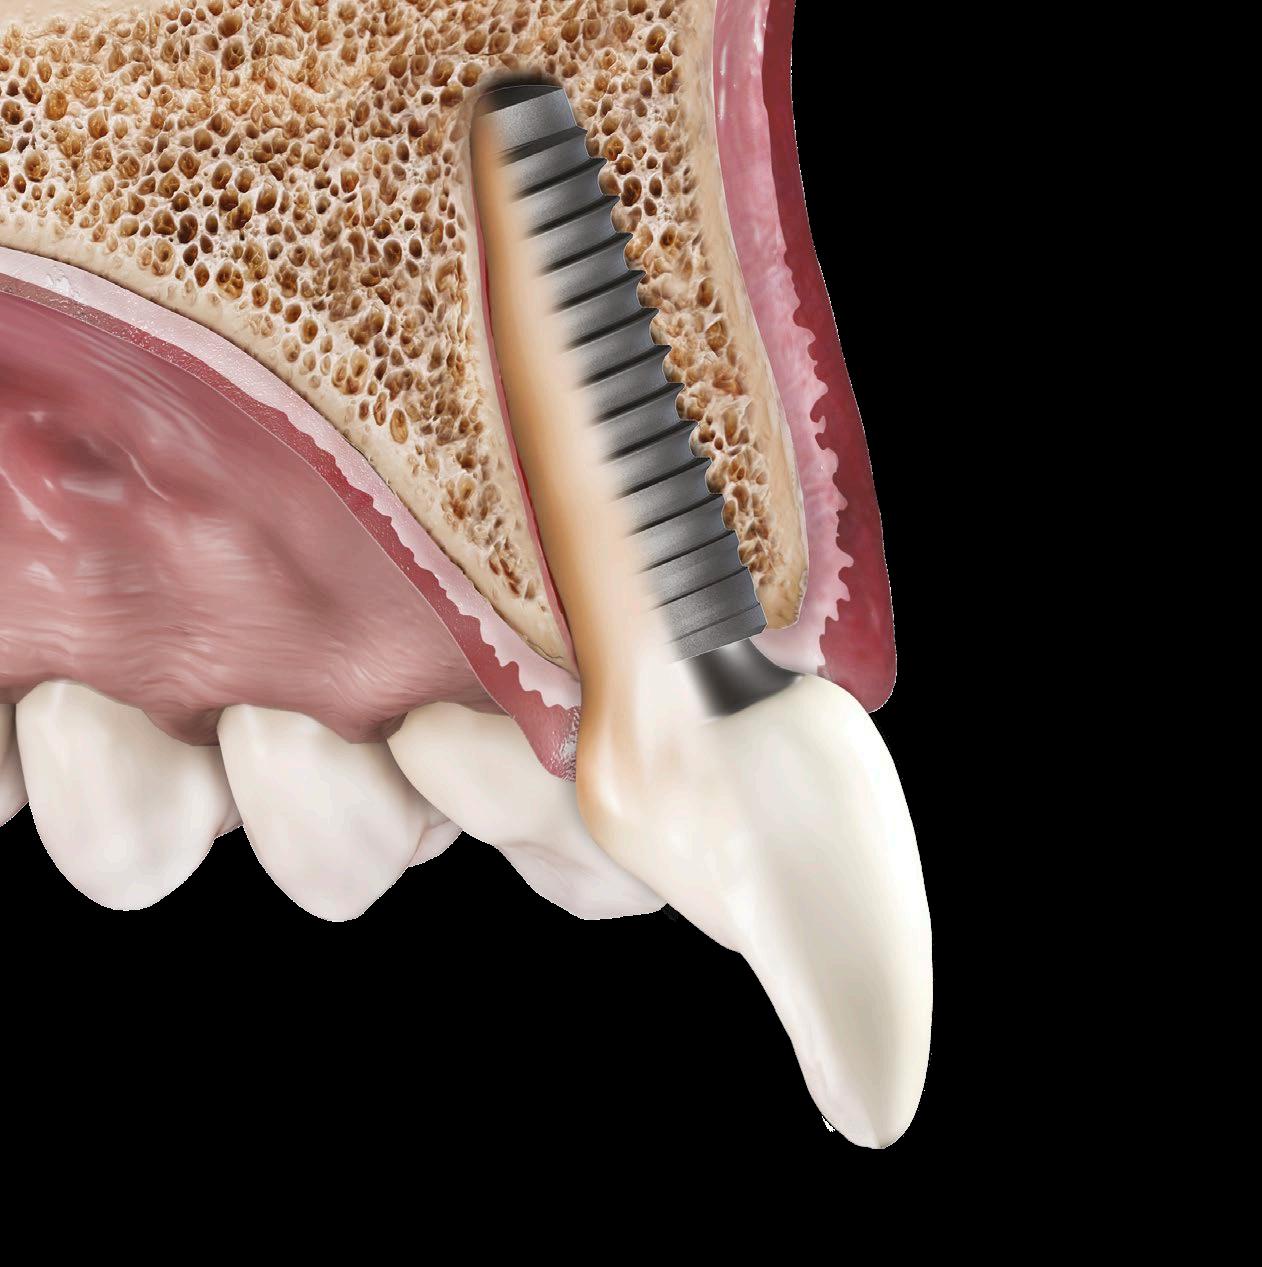

Náhrada závažně kompromitovaného

zubu imediátní implantací

Matteo Antonio Deflorian, Fabio Galli, Fabio Gorni, Pierfrancesco Zuffetti, Andrea Pittaluga, Riccardo Scaini, Tiziano Testori

Imediátní implantace po extrakci